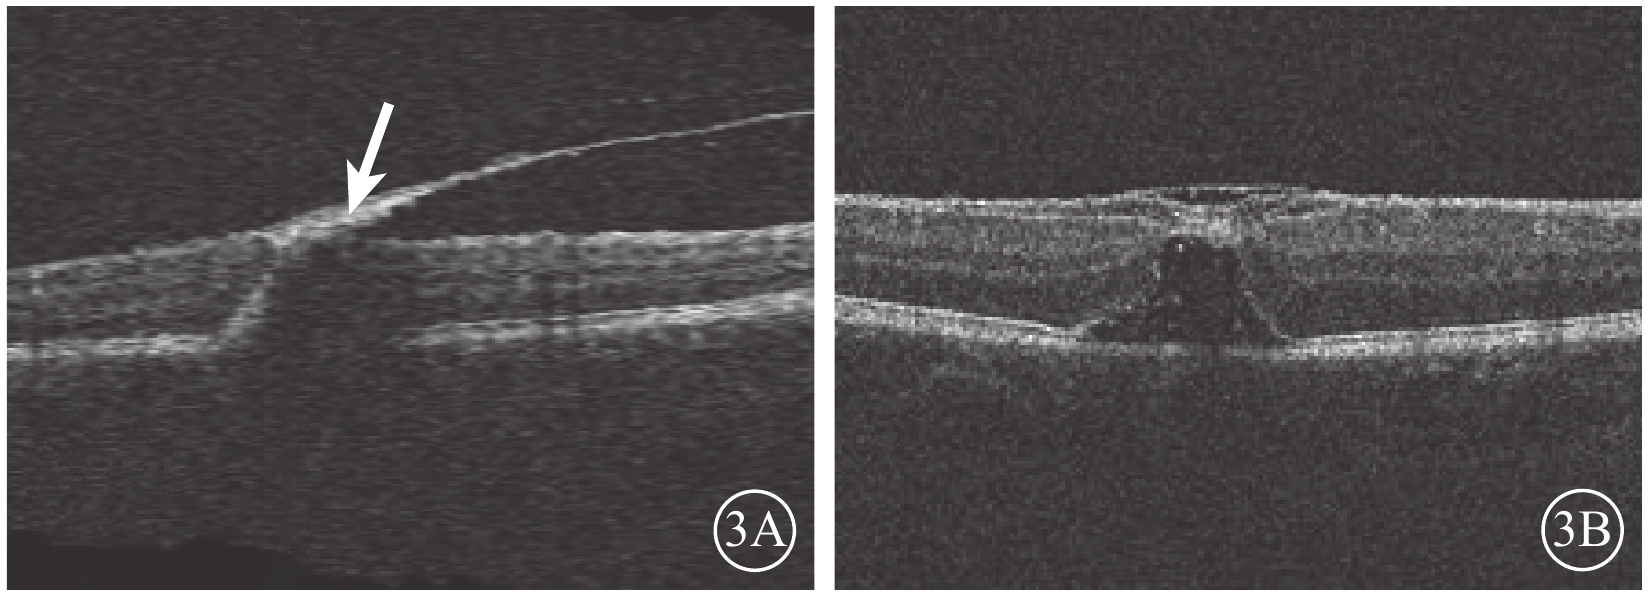

2015年12月7日行摻釹釔鋁石榴石(Nd:YAG)激光積血區內界膜(ILM)切開,最大能量3.5 mJ,單脈沖爆破模式,未見新鮮血液流出。未進行治療觀察。2016年1月27日復查,下方積血吸收邊緣至黃斑區(圖2A)。OCT檢查,黃斑區前ILM增厚,牽拉黃斑中心凹,黃斑正常結構消失(圖2B)。2月23日復查,右眼矯正視力0.25。黃斑區視網膜前出血基本吸收。OCT檢查,黃斑區ILM增厚,可見黃斑板層裂孔(圖3A)。4月20日復查OCT,黃斑中心凹處ILM增厚,中心凹鼻側ILM與其下視網膜組織分離,可見黃斑板層裂孔。仍未治療繼續觀察。8月17日復查,患者訴視物有水波紋樣浮動。OCT檢查,病變處ILM與其下視網膜組織分離,黃斑板層裂孔,黃斑中心凹處ILM較前略增厚(圖3B)。FFA檢查,黃斑拱環縮小,視網膜毛細血管變形稍紆曲,未見熒光素滲漏,可見線狀遮蔽熒光。

圖3

右眼OCT像。3A. 黃斑區ILM增厚,黃斑板層裂孔形成(白箭);3B. 黃斑區ILM與其下視網膜組織分離,黃斑區可見板層裂孔

圖3

右眼OCT像。3A. 黃斑區ILM增厚,黃斑板層裂孔形成(白箭);3B. 黃斑區ILM與其下視網膜組織分離,黃斑區可見板層裂孔

2015年12月7日行摻釹釔鋁石榴石(Nd:YAG)激光積血區內界膜(ILM)切開,最大能量3.5 mJ,單脈沖爆破模式,未見新鮮血液流出。未進行治療觀察。2016年1月27日復查,下方積血吸收邊緣至黃斑區(圖2A)。OCT檢查,黃斑區前ILM增厚,牽拉黃斑中心凹,黃斑正常結構消失(圖2B)。2月23日復查,右眼矯正視力0.25。黃斑區視網膜前出血基本吸收。OCT檢查,黃斑區ILM增厚,可見黃斑板層裂孔(圖3A)。4月20日復查OCT,黃斑中心凹處ILM增厚,中心凹鼻側ILM與其下視網膜組織分離,可見黃斑板層裂孔。仍未治療繼續觀察。8月17日復查,患者訴視物有水波紋樣浮動。OCT檢查,病變處ILM與其下視網膜組織分離,黃斑板層裂孔,黃斑中心凹處ILM較前略增厚(圖3B)。FFA檢查,黃斑拱環縮小,視網膜毛細血管變形稍紆曲,未見熒光素滲漏,可見線狀遮蔽熒光。

圖3

右眼OCT像。3A. 黃斑區ILM增厚,黃斑板層裂孔形成(白箭);3B. 黃斑區ILM與其下視網膜組織分離,黃斑區可見板層裂孔

圖3

右眼OCT像。3A. 黃斑區ILM增厚,黃斑板層裂孔形成(白箭);3B. 黃斑區ILM與其下視網膜組織分離,黃斑區可見板層裂孔